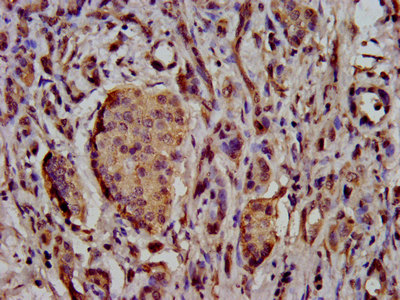

IHC image of CSB-PA883417LA01HU diluted at 1:500 and staining in paraffin-embedded human pancreatic cancer performed on a Leica BondTM system. After dewaxing and hydration, antigen retrieval was mediated by high pressure in a citrate buffer (pH 6.0). Section was blocked with 10% normal goat serum 30min at RT. Then primary antibody (1% BSA) was incubated at 4°C overnight. The primary is detected by a biotinylated secondary antibody and visualized using an HRP conjugated SP system.